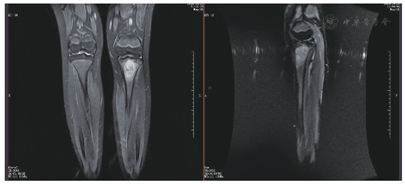

在自行停药3个月后,患者在肩峰处再次扪及肿物,于2019年12月12日再次返我院全麻下行右锁骨尤文肉瘤术后化疗后复发扩大切除术。术后病理结果:(右侧肩背部)小圆细胞恶性肿瘤,结合病史及形态,考虑为尤文肉瘤复发。2020年2年20日开始行术后辅助放疗,PGTVtb 56Gy分28次,PCTV50.4Gy分28次,共完成28次放疗。患者出院后于2020年9月2日出现左胫骨内侧隐痛可忍受,当地医院就诊,左膝关节DR结果:未见异常。未予处理。2020年10月6日左胫骨内侧疼痛加剧,2020年10月9日我院MRI提示右侧锁骨术区未见肿瘤复发(图2)。左侧胫骨干骺端-骺板-骨骺区骨质破坏,于2020年10月16日行左胫骨肿物穿刺活检术,术后病理结果:(左胫骨肿物)结合病史,符合尤文肉瘤。完善相关检查,排除其他部位的转移后,考虑患者为左胫骨上端孤立性复发转移,遂于2020年10月29日行左胫骨近端肿瘤扩大切除、人工肿瘤假体置换术。目前患者仍在我院接受后续的辅助治疗。